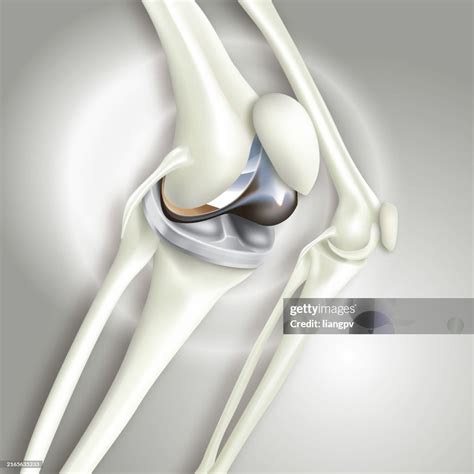

Here is an example of knee replacement images that highlight the benefits of the procedure:

Knee Replacement Benefits

📸 Note: The images above are for illustrative purposes only. Always consult with a healthcare provider for personalized information.

• Implant Placement: The artificial components are placed and secured with cement or other fixation methods.